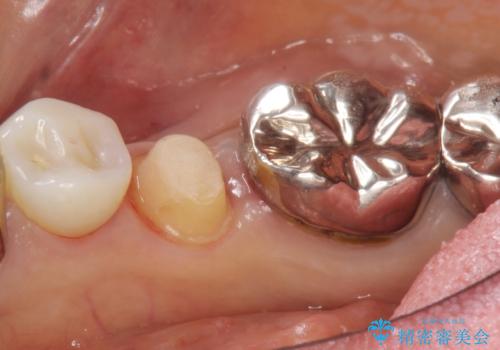

精査したところ、被せ物を入れたばかりの右下の小臼歯(右下5)は不可逆性歯髄炎により神経をとる処置(抜髄)が必要な状態でした。

根管治療後、セラミッククラウンによる補綴治療を行いました。

根管治療により痛みがなくなり、ご安心頂けました。

セラミッククラウンの自然な仕上がりにも喜んで下さいました。